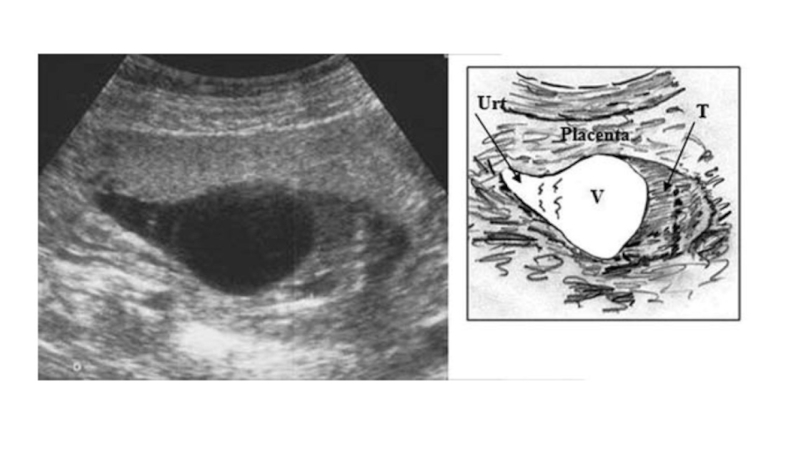

Двусторонний гидронефроз (растянутый и утолщенный мочевой пузырь)

Расширение простатической

уретры

Гипертрофия шейки мочевого пузыря (признак замочной

скважины – keyhole)

Дивертикулы мочевого

пузыря

Расширение ВМП

Олигогидрамнион

Повышенная эхогенность почки